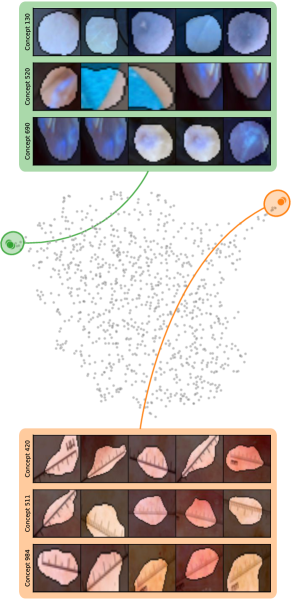

Model Perspective

Next, we apply bias identification approaches from the model perspective by identifying outlier neurons based on activation pattern via DORA and relevance pattern by clustering pair-wise cosine distances between concept relevance scores. We focus on latent activations and relevances after the third residual block. DORA uses a distance function based on how neurons activate upon each others n-AMS, achieving high similarity when neurons activate upon similar input signal. A 2D visualization of the resulting distance matrix is shown in Fig. 6 (bottom left). Identified outlier concepts include ruler () and (white) hair (). We further compute pairwise cosine distances between latent relevance scores , aggregated over spatial dimensions, and apply UMAP to embed the resulting distance matrix in . This results in high similarity between neurons (concepts) that the model uses similarly for predictions. The concept clustering is visualized in Fig. 6 (bottom right), highlighting two outlier clusters focused on rulers () and blueish tint ().

Results for other classes, model architectures, and datasets are presented in Appendix A.6.1. This includes experiments with ECG data in Fig. 10, revealing the artificially inserted static noise in the attacked lead from both data and model perspectives. Notably, dominant spurious concepts, such as the artificial timestamp in HyperKvasir or the static noise in PTB-XL, may not be detected as outlier concepts. In such cases, analyzing prediction sub-strategies via PCX may provide additional insights on spurious inlier behavior. Hard-to-interpret concept representations pose another challenge for the model perspective. For example, the brightness artifact in CheXpert is not clearly visible in the concept UMAP (see. Fig. 15, right), but can easily be detected using SpRAy (Fig. 15, left) or PCX (Fig. 22). In summary, while all considered spurious features are detected, the choice of bias identification approach is crucial, as some shortcuts are easier to detect as outlier concept (e.g., ruler) and others via PCX (e.g., brightness, static noise in ECG).